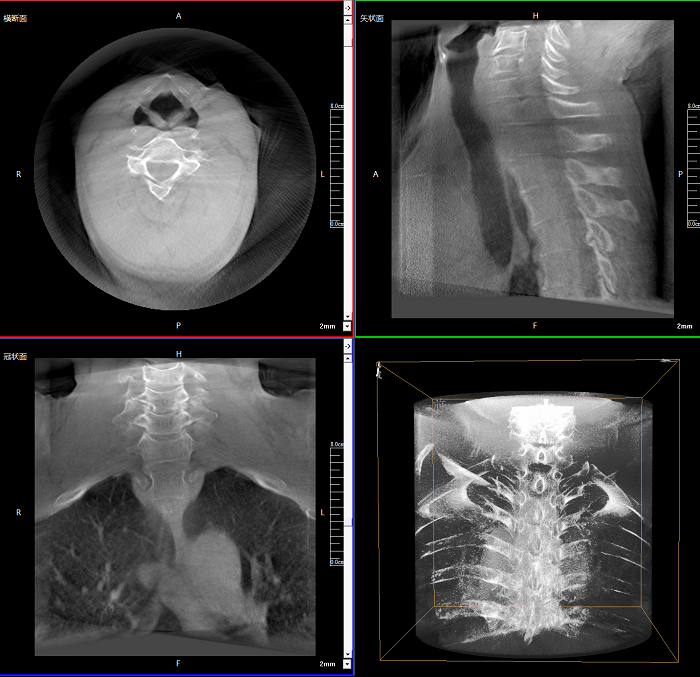

該設(shè)備可進(jìn)行快速的術(shù)中三維掃描,生成類CT斷層圖像和立體3D圖像,保障植入物置入效果。廣泛適用于骨科、脊柱外科、矯形外科、創(chuàng)傷骨科等其他領(lǐng)域。

●極速成像僅需8秒,從數(shù)據(jù)采集結(jié)束到完成三維重建斷層影像